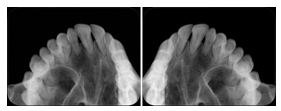

3. A dental provider wishes to capture a series of DICOM IO images for the patient’s dentition. The tooth morphology, teeth are divided into molars, premolars, canines and incisors, and a number of images for each jaw. The anatomic information was captured utilizing the triplet of schema. This standard code sequence is based on ISO 3950-2010, Dentistry - Designation system for teeth and areas of the oral cavity.

Every IO image should have anatomic information either through the primary or modifier sequence.

In most standard cases, images are oriented in structured layouts. These structured displays are useful to be shared between providers for reference purposes.

Table OO.1.1-1 shows structured display standard templates, where Viewset ID is based on the Japanese Society for Oral and Maxillofacial Radiology (JSOMR) classification provided by JIRA (Japan Medical Imaging and Radiological Systems Industries Association, www.jira-net.or.jp). Expected or typical teeth to be imaged location, region and designation codes are based on ISO 3950-2010, Dentistry - Designation system for teeth and areas of the oral cavity. For all the hanging protocols listed in OO.1.1-1, the value to use for Hanging Protocol Creator (0072,0008) is "JSOMR" and the value to use for Hanging Protocol Name (0072,0002) does not include "JSOMR" (e.g., "DL-S001A", not "JSOMR DL-S001A").